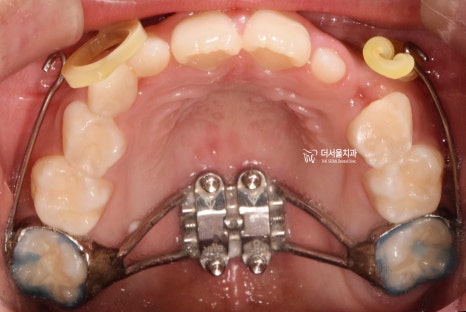

『페이스 마스크(face mask) 사용』

착용 전

착용 후

악궁 확장장치와 페이스마스크를 사용했습니다.

요즘은 잘 안 쓰죠?

구외장치도 같이 껴야 되기 때문에

심미성이 떨어지면서, 아이들이 싫어합니다.

왜냐하면 친구들이 많이 놀리고,

하루에 대다수 시간을 끼고 있어야

효과를 볼 수 있기 때문이죠.

(이때는 인비절라인 퍼스트가 없었습니다.)

그렇게, 페이스 마스크 및 악궁확장장치를

끼니 윗니가 아랫니가 덮는 overjet 이

형성 되어있는 것을 볼 수 있네요.